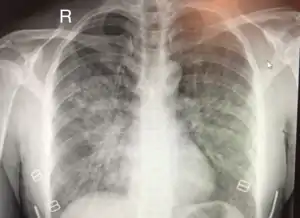

| Chest x-ray of HAPE showing characteristic patchy alveolar infiltrates with right middle lobe predominance. | |

Hypoxic pulmonary vasoconstriction (HPV) occurs diffusely, leading to arterial vasoconstriction in all areas of the lung. This is evidenced by the appearance of "diffuse," "fluffy," and "patchy" infiltrates described on imaging studies of climbers with known HAPE.[7]

On physical exam, increased breathing rates, increased heart rates, and a low-grade fever 38.5o (101.3o F) are common.[7][8] Listening to the lungs may reveal crackles in one or both lungs, often starting in the right middle lobe.[7][8] This can be seen on X-ray and CT imaging of the chest.[7][8] One distinct feature of HAPE is that pulse oximetry saturation levels (SpO2) are often decreased from what would be expected for the altitude. People typically do not appear as ill as SpO2 and chest X-ray films would suggest.[7][8] Giving extra oxygen rapidly improves symptoms and SpO2 values; in the setting of infiltrative changes on chest X-ray, this is nearly pathognomonic for HAPE.[8]

Severity